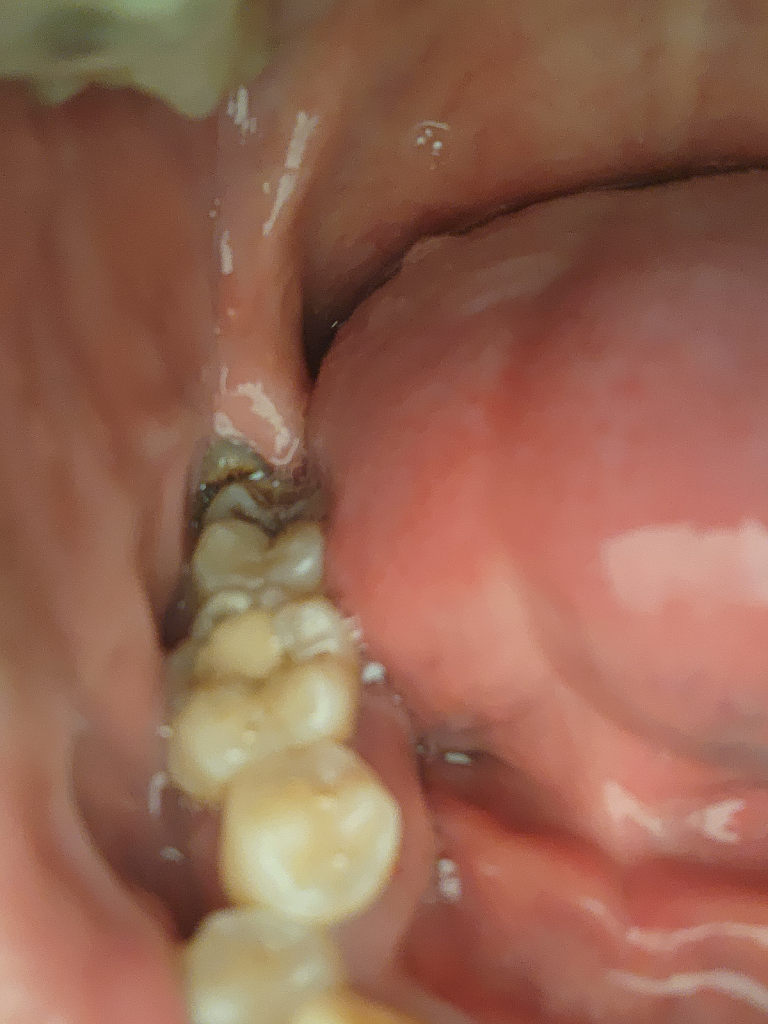

안녕하세요 매복사랑니 질문 드리겟습니다.

저 사진 끝과 같이 앞에 살짝나온 머리부분 사랑니이구요 낼 모레 발치 예정인데 수술 난이도 정도 어떨가요? 상중하 로 따지면요

• 1번 째 사진

구강내 사진으로는 난이도를 판단하기는 어렵고 엑스레이 사진을 잇어야 어느정도 예상을 할수 있습니다.

사랑니 엑스레이를 봐야 알 수 있지만 치아가 잇몸밖으로 나와있어 중 정도 될 것으로 보입니다.

난이도 평가는 아래턱 신경관과의 위치, 사랑니 뿌리 모양, 옆어금니나 잇몸뼈와 겹친 정도를 x-ray상에서 평가합니다 지금 사진상으로는 단지 부분매복 사랑니가 앞쪽으로 기울어져 나있다는 것밖에 알 수 없습니다